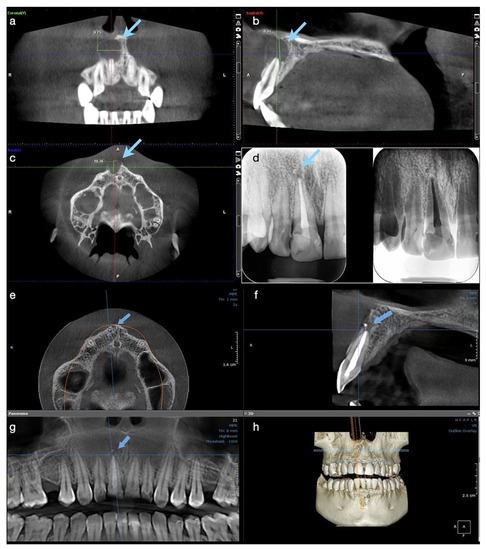

A CBCT investigation was recommended for the upper anterior teeth and performed in the dental clinic with the following parameters: 8 × 15 cm field of view, 250 µm voxel size, 90 kV, 7.1 mA, and 8.14 s emission. On the CBCT images analyzed on the 25” Dell monitor with a 1920 × 1080 pixel resolution, a large unilocular radiolucent lesion which involved the periapical region of tooth #11 was observed, extending towards the mesial region. It exceeded the middle maxillary line and was also involving the mesial part of the apical root third of tooth #21. In an upper direction, it was extending to the nasal fossa, presenting an intact nasal floor.

The size of the lesion was measured using the measurement tools of OnDemand3D (OP 3D™ Pro, KaVo Dental GmbH) and was about 15 mm in height, 13 mm in the buccolingual direction, and 13 mm in the mesiodistal. The lesion appeared well contoured by a thin radiopaque border line on all its contours, communicating with the apex of tooth 11 in its inferior part (presumptive diagnosis of pocket cyst) (Figure 2a–d). In addition, on the CBCT scan, teeth #21 and 22 appeared to be endodontically treated, with a radio-opaque obturation material present in the root canal space, 3 mm shorter from the radiographic apex for tooth #21 and 2 mm shorter for tooth #22. A small area of radiolucency of about 1 mm diameter around the apex of tooth #22 was also observed.

In order to decrease the pressure and to favour the drainage of the exudate from the periapical area of tooth #11, after local anaesthesia, a small incision in the mobile buccal mucosa was performed in the same session with a Bard-Parker surgical blade no. 15, disrupting the cystic wall. Immediately after the incision, a yellow straw-coloured fluid with a dense consistency, containing blood, pus, and cholesterol crystals, was observed draining from the lesion (Figure 2e).

Approximately 10 mL of metronidazole solution 5 mg/mL (Metronidazole B, Braun, Germany) was delivered into the lesion until a clear exudate was observed. A drainage tube was placed into the small window surgically created in the lesion’s buccal wall and was then sutured at its edges, so the drainage remained efficient (Figure 2f). The tube was removed after two days, and two weeks later the patient presented for the completion of the endodontic treatment. After the removal of the intra-canal dressing, the root canal could now be completely dried and obturated using the continuous wave of condensation technique. Post-operative instructions were given to the patient and she was scheduled for recall at three months.

At the three-month follow up, the buccal bone in the central incisor’s area became consistent at palpation, and the patient described no symptoms during this period of time or at the clinical exam. At the 6-months control, the patient was subjected to another CBCT investigation. A significant reduction in the size of the periapical lesion in a buccolingual direction, from 12 mm to 5.88 mm, and in a mesiodistal direction, from almost 13 mm to 7.70 mm, was observed with the continued increase in density of the new trabecular bone in all three plans (Figure 2g–j). The total height of the lesion was reduced from 8.26 mm to 5 mm, and the cortical buccal plate appeared significantly wider and mineralized.

Figure 2. Case 2. Radiological investigations and clinical images of tooth #11: (ad) Initial CBCT scans with the measurements of the lesion size: 12.10 mm in buccolingual direction, 8.26 mm in height, and 12.49 mm mesiodistal diameter, with the buccal cortical plate resorbed (12.10 × 8.26 × 12.49 mm); (e,f) The surgical procedure of decompression at the end of the endodontic treatment with the appearance of yellow fluid draining from the lesion, and the drainage tube fixed with sutures on the mucosa; (gj) CBCT scans and the 3D reconstruction at 6 months after the endodontic therapy, with the formation of new bone and increased reduction of the lesion size, starting from its periphery (5.88 × 5.10 × 7.70 mm).